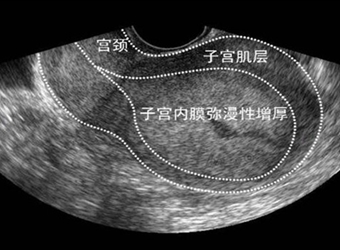

子宫内膜增厚是女性子宫疾病的其中一种情况,引起子宫内膜增厚的原因有很多,它会给女性带来许多麻烦,比如月经量比别人的多,会引起阴道异常出血的情况等,接…

我月经都推迟一个月没来了,这期间我并没有怀孕,上一次去医院还做了全面的身体检查,检查结果是子宫内膜增厚,真搞不懂子宫内膜增厚是怎么回事,这是一种比较…